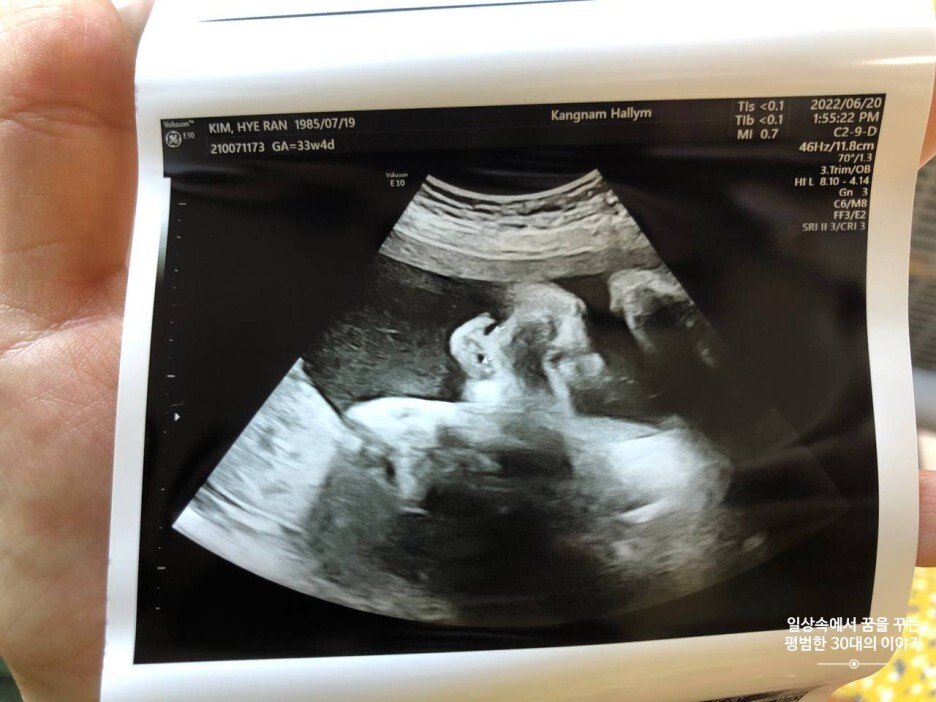

6월 20일 월요일(33주차 4일)

BPD(Biparietal Diameter, 위에서 볼 때 태아 머리 단면의 가장 긴 길이): 8.26cm

HC(Head Circumference, 태아 머리둘레): 29.98cm

AC(Abdominal Circumference, 배 둘레): 32.6cm

EDD(Expected Date of Delivery, 출산 예정일): 2022년 8월 4일

FL(Femur Length, 허벅지뼈 길이): 6.53cm

GA(Gestational Age, 임신 주차): 33주 차 4일

EFW(Estimated Fatal Weight, 태아 예상 체중)=EBW(Estimated Body Weight): 2600g

FHR(Fetal Heart Rate, 심장박동 수): 154bpm

CL(Cervical Length, 자궁경부 길이): 정상

AF(Amniotic Fluid, 양수): 정상

3주 만에 정기검진받으러 방문한 산부인과. 회음부가 너무 부어 점점 걷기가 불편하고 피가 속옷에 묻어 나오는 경우도 있어서 걱정이 되기 시작했었다. 혹시 자궁경부 길이가 짧아진 것은 아닌지 조산기가 있는 건 아닌지... 그리고 조금만 움직여도 숨이 차고 조금만 무리해서 먹으면 토할 것 같이 속이 더부룩하고 다리에 경련도 잦아졌다. 초산이다 보니 어떤 증상이 있어도 그 이유를 알기가 어렵기 때문에 점점 걱정인형이 돼가는 것 같다. 그래서 걱정거리를 한가득 가지고 의사선생님께 그동안 궁금했던 것들을 물어보았다. 다행히 자궁경부 길이도 정상이고 질염도 없고 조산기도 없단다. 그런데 회음부가 다른 임산부에 비해 심하게 부은 건 사실이라고 절대 무리하지 말고 누워있거나 다리를 높이 올려놓고 있는 게 좋다고 하셨다.(아기가 주차 수에 비해 크다는 것, 아기가 너무 활발하다는 것 그리고 아래쪽 혈액순환이 잘 안되는 것이 그 원인일 수 있다고 하셨다.) 그리고 아기가 지금 너무 커서 이 상태면 40주에 4kg까지 커질 수도 있다고... 그 말은 내가 그토록 원하던 자연분만이 어려워질 수도 있다는 말... 게다가 역아!! 머리를 아주 위쪽으로 향한 채 다리를 빵빵 차대고 있으니;;; 나의 의지와 상관없이 유도 분만이나 제왕절개를 해야 할 수도 있다고 한다. 우선 3주 뒤에 있을 정기검진에서 아기의 상태를 본 후 결정을 내리자고 하셨다. 언제 이렇게 많이 큰 거니 이안아;;; 아기가 안 크게 하려면 걷기를 많이 해야 하는데 누워있기만 하라고 하시니 대체 이를 어찌해야 할지;;